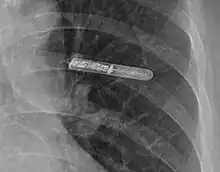

Le moniteur cardiaque implantable (appelé aussi moniteur électrocardiographique implantable[1] ; en anglais, implantable loop recorder ou ILR) est un dispositif médical, de la taille d'un briquet, implanté sous la peau, permettant d'analyser l'électrocardiogramme en temps réel et d'enregistrer automatiquement ou manuellement un certain nombre de tracés qui doivent être validés secondairement par le médecin.

Elle se fait sous anesthésie locale après soins d'asepsie chirurgicale, sous la peau au niveau de la partie médiane gauche du thorax.